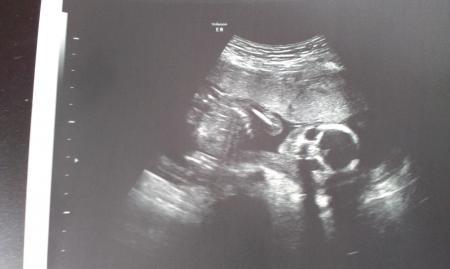

Ich bin heute aus dem Geschäft gehetzt, um rechtzeitig bei meiner FA anzukommen. Die Hektik hat sich natürlich gelohnt und ich bin jetzt wieder total erleichtert, dass alles ok ist!!! Unser Bärchen ist zeitgemäß entwickelt und hat sich fleißig bewegt. Zuerst haben wir nur zwei Hände gesehen, die gewunken haben. Meine Ärztin war auch ganz begeistert, da sie sowas noch nicht oft gesehen hat. Beim anschießenden US am Bauch hat man das Kleine komplett gesehen, allerdings wollte es uns sein Geschlecht noch nicht zeigen. Hoffentlich dann beim nächsten Termin am 26.3.! Ein Foto hänge ich auch mit ran. Den Kopf erkennt man recht gut... Kaum daheim angekommen, musste ich mit meiner Katze Lilli zum Tierarzt, weil sie heute kastriert wurde. Vorhin haben wir sie wieder abgeholt, sie ist von der Narkose aber noch total benommen und wackelig auf den Beinen. Das arme Ding!

und hier das Foto.... Und auf dem Weg zum Arzt wurde von mir auch noch ein Fot geschlossen.. (blöde Blitzer!!)